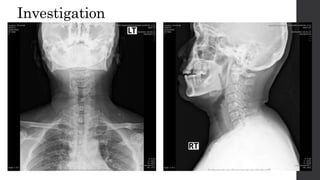

Investigation

• No gold standard for diagnosis

• Radiographs : chest radiograph and cervical spine radiographs

 cervical rib

 prominent C7 transverse process

 low lying shoulder girdle

 Pancoast tumor

Investigation • No goldstandard for diagnosis • Radiographs : chest radiograph and cervical spine radiographs  cervical rib  prominent C7 transverse process  low lying shoulder girdle  Pancoast tumor • Three-dimensional imaging CT and MRI • Nerve conduction studies • Vascular studies • Angiography